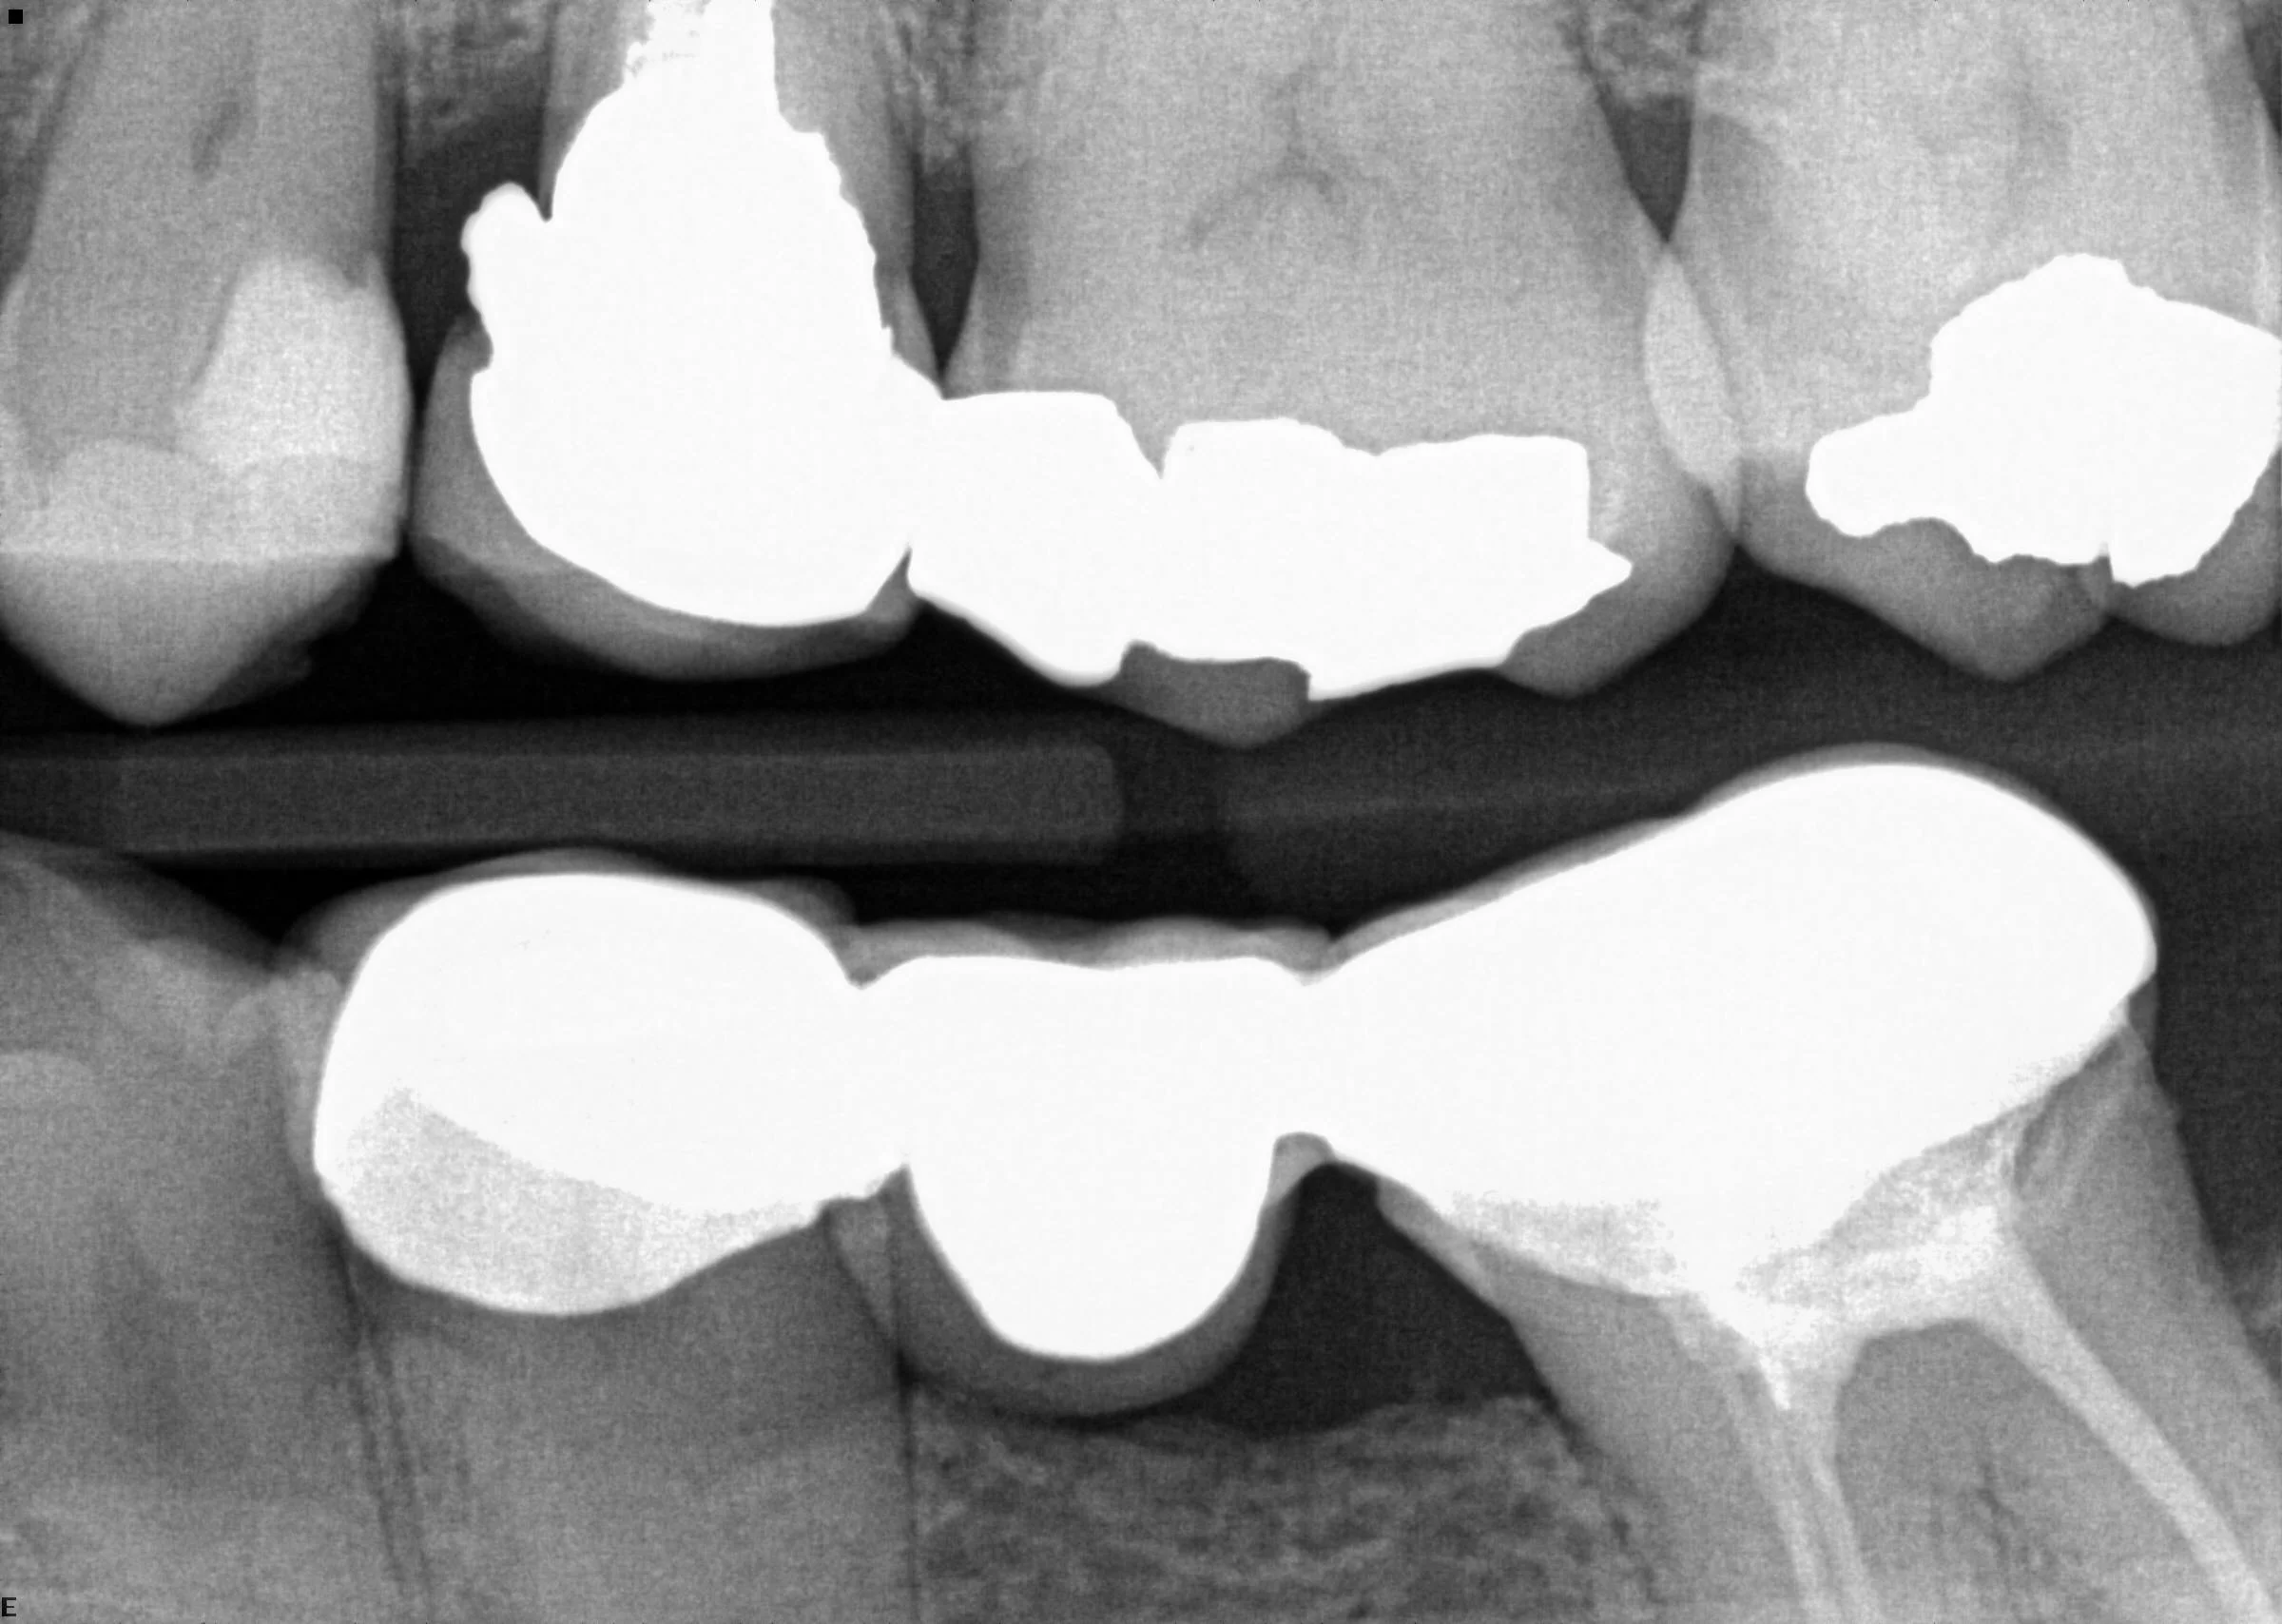

Class II composite restoration

#29DO before

#29 DO After

#13 had old PFM crown which had amalgam overhang under the mesial margin that was causing food trap and periodontal issues. I opened up the crown, removed the overhang and lowered the margin and replaced with full zirconia crown on #13 for better longevity.